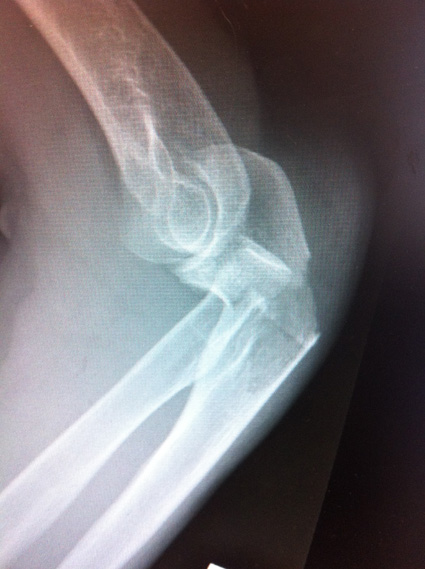

The surgeon showed her the before and after x-rays on his screen and she took a couple of photos with her iPhone. That’s certainly an impressive array of metal in the arm! Does she now qualify as a Cyberwoman?